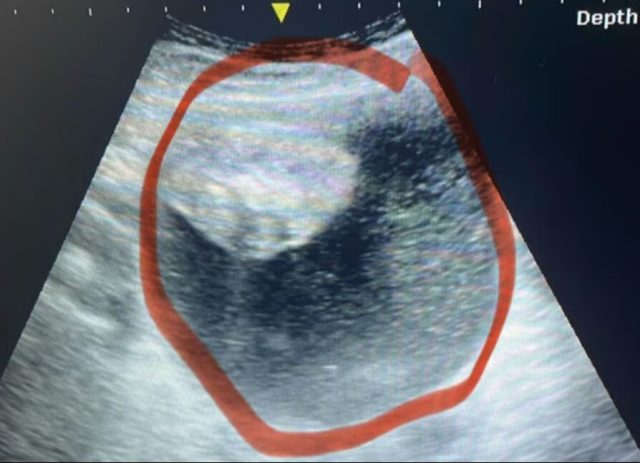

Yapılan testler sonucunda hamile olmadığı ortaya çıkan Gerrits, ultrason ve ileri tetkiklere alındı. Başta ne olduğu anlaşılamayan bu şişliğin mesaneye baskı yapan sıvı dolu bir kitle olduğu tespit edildi. Ancak kesin tanı ancak günler sonra yapılan jinekolojik muayene ile konulabildi: Yumurtalık tümörü…

Hastalığın ilerlemesi oldukça hızlıydı. Cuma günü yapılan ölçümde 12 santimetre olan kitle, Pazartesi günü 17 santimetreye ulaştı. Bu hızlı büyüme nedeniyle Gerrits acil ameliyata alındı. Tümör ameliyat sırasında patladı ancak bu durum, hastalığın yayılmadan kontrol altına alınmasında önemli bir şans olarak değerlendirildi.